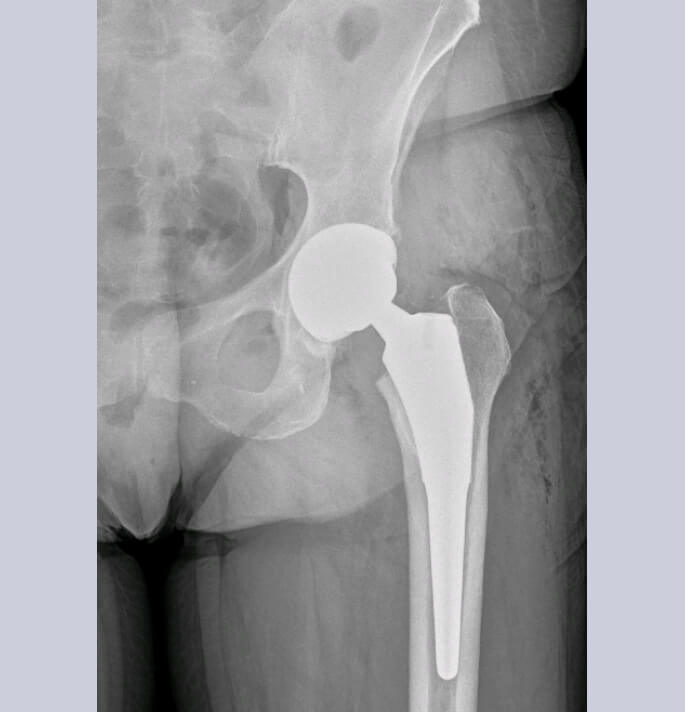

Beenderig wordt de versleten heupkop verwijderd en vervangen door een titanium cup in de heup pan (niet gecementeerde acetabulaire component) en een niet gecementeerde titanium heupsteel welke in het mergkanaal wordt ingebracht. In de metalen cup van het acetabulum wordt een glijlaag (liner) in polyethyleen of ceramiek ingebracht.

Op de femorale component wordt dan een bijpassend kopje in metaal of ceramiek geplaatst.

Patiënten voor een heupartroplastie worden opgenomen in het ERAS (ENHANCED RECOVERY AFTER SURGERY) traject. Door intense samenwerking en afstemming van de activiteiten van zowel logistiek, verpleging, kinesitherapie, ergotherapie, anesthesie en chirurgie wordt een geoptimaliseerd herstel beoogd wat ons ook toelaat om in geselecteerde patiënten dergelijke chirurgie via daghospitaal aan te bieden.